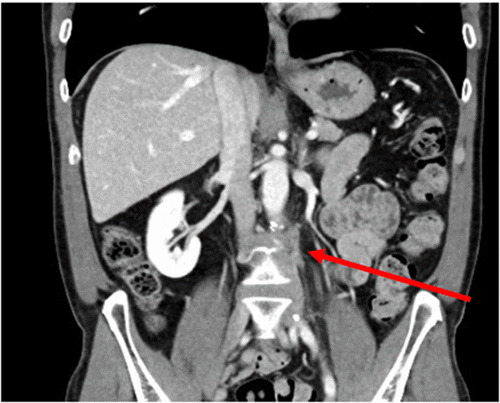

In anticipation of a technically challenging dissection due to prior surgery and radiation, MOLLI Markers® (magnetic seeds) were placed percutaneously by interventional radiology under CT guidance two weeks before the planned operation. These markers were positioned just cephalad and caudal to the recurrent lesion to facilitate intraoperative localization (Figure 2). A left ureteric stent was also placed preoperatively. The abdomen was entered via a lower midline incision, and the aortic bifurcation was exposed. The MOLLI markers were easily identified using a handheld magnetic probe, and superficial marking stitches were placed on the overlying retroperitoneal tissues to visually bracket the target area. Dissection revealed a short IMA remnant coursing leftward over the fibrotic tumor mass. Consistent with the patient's history, all surgical planes were densely fibrotic. The MOLLI markers proved critical in guiding the vertical extent of the dissection. The most demanding portion of the procedure involved sharp dissection to develop a plane between the adventitia of the aorta and the recurrent tumor mass.

Figure 2. CT Confirmation of Magnetic Seed (MOLLI Marker®) Placement. Published with Permission

Coronal reformatted CT scan obtained after percutaneous, image-guided placement of MOLLI Markers®. The image demonstrates the precise positioning of the magnetic seeds (arrows) bracketing the recurrent para-aortic lesion, confirming their suitability for intraoperative localization